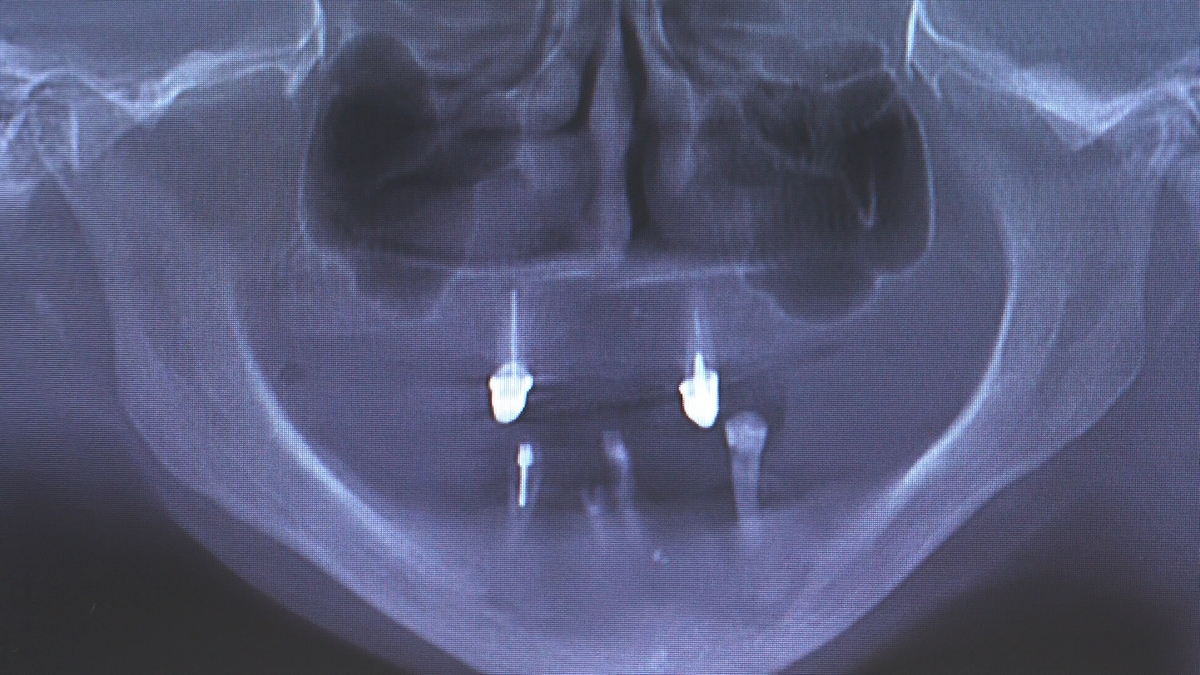

W trakcje dwóch dni zabiegowych, piątek i sobota, 5 i 6 października 2018 roku, lekarze uczestniczący w 6 Sesji VI Sezonu, wykonali wiele zabiegów o wysokim stopniu trudności. Przeprowadzili je pod kierunkiem Mentorów Instytutu Vivadental – dr n.med. Violetty Szycik, dr n.med. Magdaleny Kisłowskiej-Syryczyńskiej oraz dr Małgorzaty Piotrowskiej.

Wprowadziliśmy łącznie 25 implantów w tym wykonaliśmy:

dwa zabiegi All- on -4 / jeden w szczęce, jeden w żuchwie/ z usunięciem zębów i natychmiastową implantacją oraz natychmiastową odbudową protetyczną